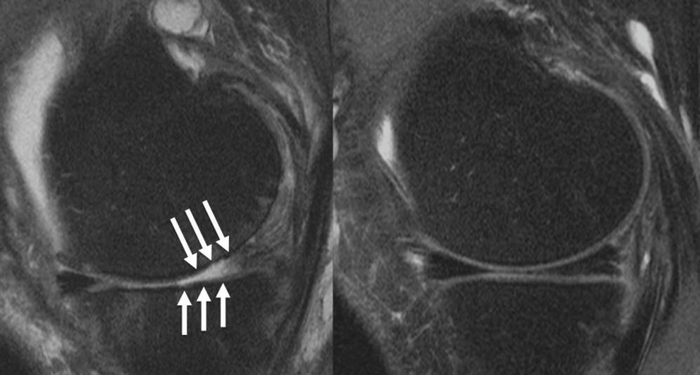

图片:患者的膝关节(a)显示严重的软骨缺损和(B)完整的膝关节。

图片来源:RSNA和Upasana Upadhyay Bharadwaj医学博士